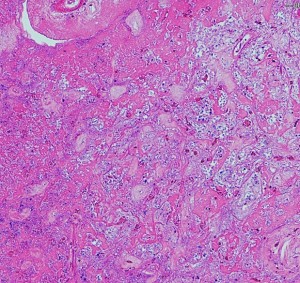

病理所見です

古い用語で凝固壊死 coagulation necrosisという言葉がもっとも適切に病理像を表しています。放射線による血管内皮のダメージで血管壁がヒアリン化して閉塞して虚血となります。また乏突起膠細胞がダメージをうけて髄鞘が脱落します(脱髄)。その結果,炎症と組織修復のための新生血管増殖が生じて脳間質組織浮腫が生じます。IL-1, TNF, IL-6などの炎症惹起性サイトカインはステロイドで抑えられます。同時に,この過程ではreactive astrocytesから多量のVEGFが産生されこれが放射線壊死による脳障害の主因と考えられています。VEGFは血管透過性 vascular permiabilityを増大させるので,組織間浮腫が高度なります。

左,壊死像と脳の境界領域。右,壊死層の中の大小の血管の閉塞像とマクロファージの浸潤がみられます。動脈壁のヒアリン化 hyaline thickening/hyalinizationと血管内腔の閉塞も特徴的な所見です。脳組織は中心部で虚血壊死になり,周囲組織での神経細胞のアポトーシスや白質変性も同時に進行します。この様な部位からの組織低酸素状態で誘発されるVEGFの産生と炎症惹起物質(TNF-alphaなどのサイトカイン)が,細血管からの血漿成分の漏出をまねき脳組織浮腫や慢性炎症を引き起こすと考えられています。fibrinoid deposition, fibrogliosisや微小石灰化の所見を伴うこともあります。

周囲の正常構造を保っている周囲脳組織内の反応性グリア細胞,豊富な好酸性胞体を有するreactive astrocyte(左下の赤い細胞)が多数見られます。 血管新生が盛んに生じていて拡張した毛細血管のような血管構造 telangiectasisが増加します。

放射線壊死の活動期は半年から2年くらいです。その後には脳壊死の部分が萎縮し周囲の脳浮腫は消褪します。組織学的には壊死巣は瘢痕組織となります。中心部は肉芽腫となり周囲にはgliofibrosisを残します。